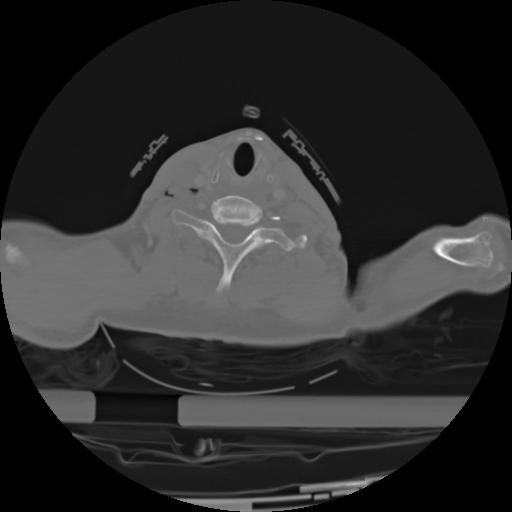

21 ANGIO,CE,Axial,3.0,ANGIO,,